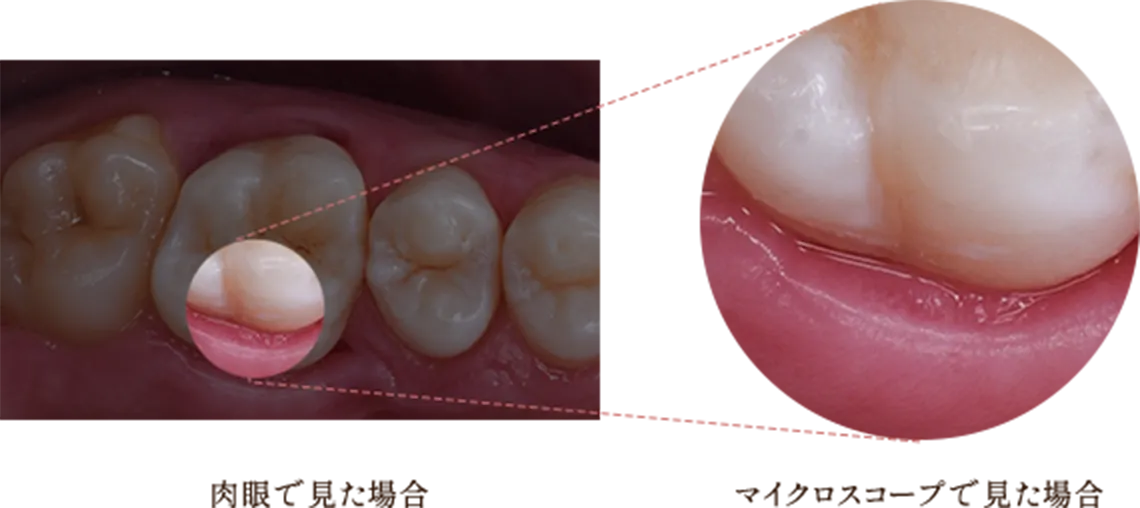

歯の内部における疾患は、歯髄の細菌感染が原因であるため、その細菌を取り除くことが根管治療の本質です。マイクロスコープを使用することで、肉眼に比べ約26倍の拡大視野で根管内を洗浄・除去することが可能となり、より正確な治療が行えます。その結果、再発のリスクを軽減し、歯を残せる成功率が格段に向上します。

マイクロスコープ下の精密治療